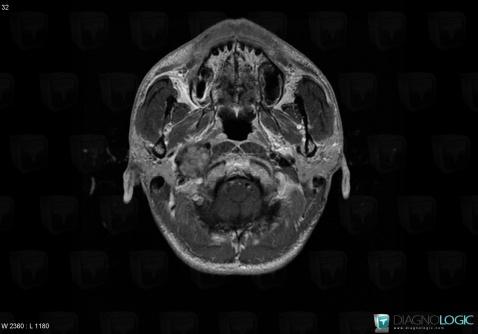

Schwannome, Espaces peri cérébraux infratentoriels, Autres nerfs craniens, IRM

Voici les informations spécifiques à l'image clé ci dessus:

- Diagnostic Schwannome, Localisation(s) Autres nerfs craniens, comportant les gammes Lésion des nerfs craniensEspaces peri cérébraux infratentoriels, comportant les gammes Lésion extra axiale infra tentorielleFosse postérieure, comportant les gammes Lésion infratentorielle en hypersignal T2 ou FLAIR